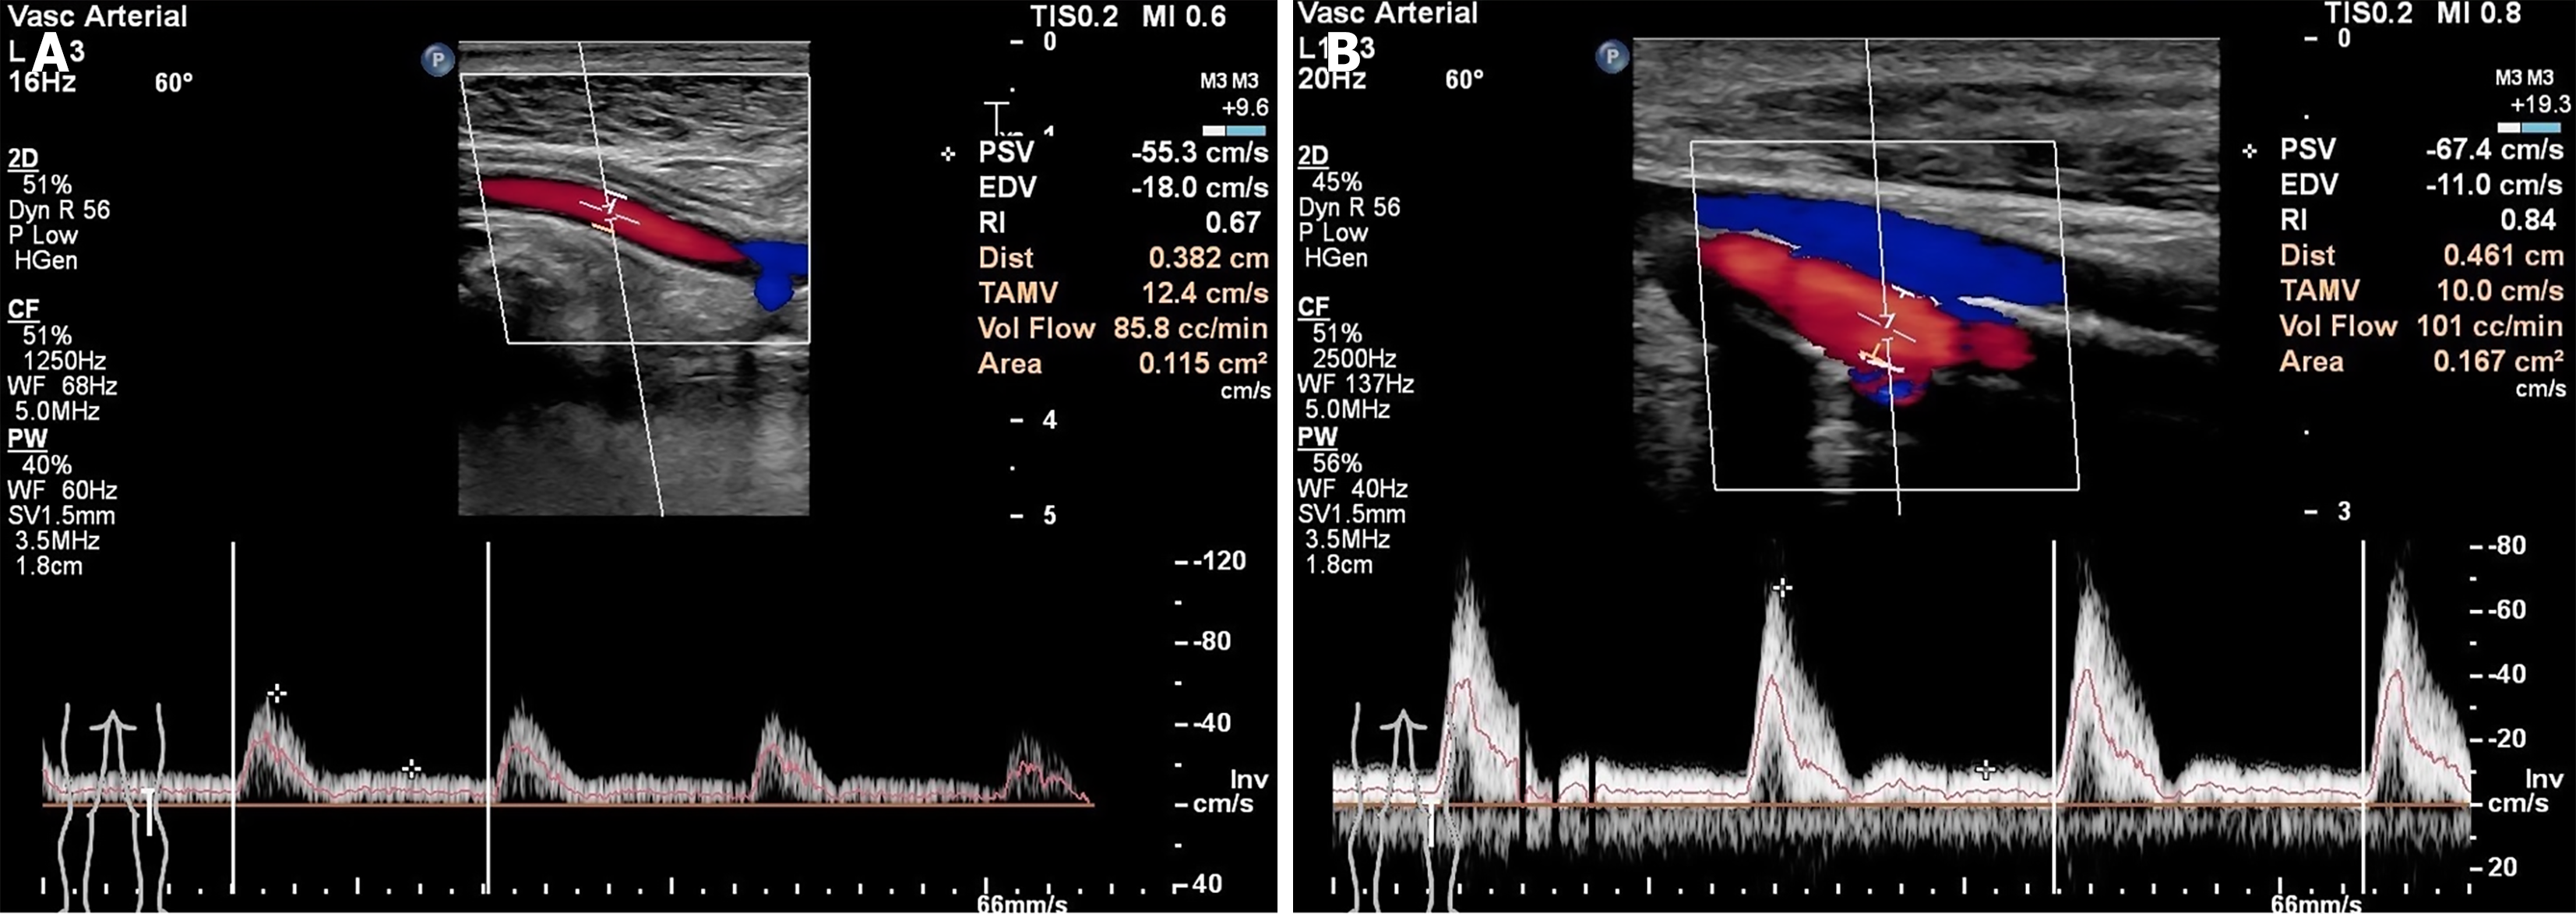

Figure 3 A patient, an elderly male with a left-sided Wagner grade 4 diabetic foot, underwent transverse tibial bone transport.

A: Popliteal arterial blood flow before the operation; B: B-ultrasound indicated a marked elevation in popliteal arterial blood flow one month after the operation. A linear array probe (frequency: 5.0-12 MHz) was employed during examination.